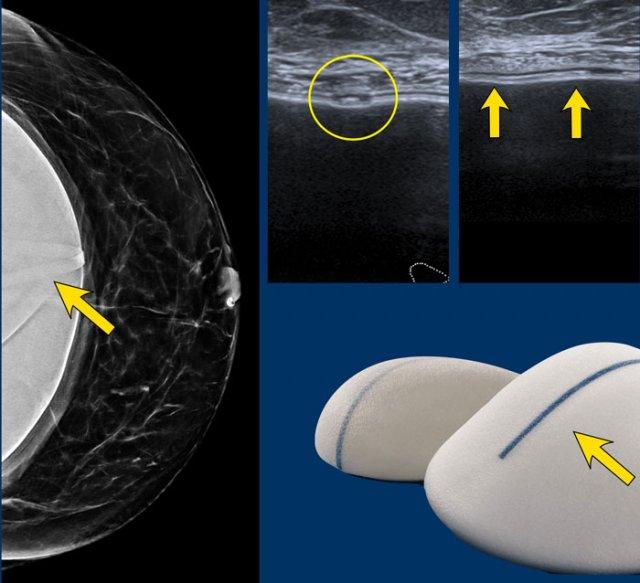

Dấu hiệu đánh dấu (Markings)

Hình chụp nhũ ảnh cho thấy túi độn ngực có một dải vòng nhỏ.

Trên siêu âm, cấu trúc này được nhận diện là một cấu trúc tuyến tính khi quan sát trên hai mặt phẳng (hình tròn trên mặt cắt ngang và các mũi tên trên mặt cắt đứng dọc).

Không nên nhầm lẫn hình ảnh này với tổn thương vỏ bọc.

Trên nhũ ảnh năm 2019 cho thấy vôi hóa bao xơ lan rộng và hình dạng rất tròn của túi độn ngực.

Điều này gợi ý co rút bao xơ của túi độn.

Tại lần tái khám năm 2020, đường bờ đã thay đổi và hiện có silicone thoát ra ngoài bao xơ, đây là dấu hiệu xác định của vỡ túi ngoài bao xơ (mũi tên).

Bệnh nhân cao tuổi này không muốn phẫu thuật mà chỉ muốn tầm soát khả năng ác tính.

Tại lần tái khám năm 2022, hình ảnh không thay đổi nhiều. Gel silicone hiện đại có độ kết dính cao hơn và ít có xu hướng lan rộng hơn.